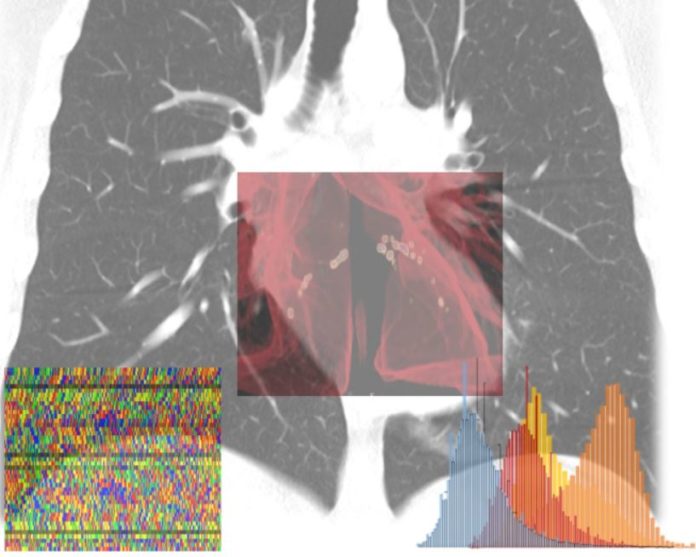

MILANO (ITALPRESS) – Una piattaforma di apprendimento autonomo in grado di calcolare per ogni individuo – sulla base di una serie di indicatori clinici e diagnostici – la probabilità di sviluppare le forme più gravi di Covid-19, permettendo così interventi sanitari mirati e tempestivi e riducendo l’impatto sul sistema sanitario. E’ questo l’obiettivo del progetto AI-SCoRE (acronimo di Artificial Intelligence – Sars Covid Risk Evaluation) ideato dai professori Carlo Tacchetti e Antonio Esposito, entrambi docenti dell’Università Vita-Salute San Raffaele, rispettivamente direttore e vice-direttore del Centro di Imaging Sperimentale dell’IRCCS Ospedale San Raffaele di Milano, e sviluppato in collaborazione con due colossi mondiali dell’information technology come Microsoft e NVIDIA, con il Centro di Omics Sciences dell’IRCCS Ospedale San Raffaele diretto dal dottor Giovanni Tonon, e con il supporto di due aziende: Orobix srl, società attiva nell’ingegneria, produzione e governance di sistemi di AI con esperienza decennale e internazionale in ambito healthcare e Porini, centro di eccellenza e partner internazionale di Microsoft sulle piattaforme Cloud Azure e sulle soluzioni di Advanced Analytics.

“L’Intelligenza Artificiale (IA) sta aiutando a combattere la pandemia in molteplici casi d’uso. Le piattaforme IA di calcolo accelerato e il software di NVIDIA sono sfruttate in tutto il mondo per aiutare a sequenziare e analizzare i genomi virali e dei pazienti, monitorare la diffusione delle infezioni e l’andamento della mobilità, accelerare lo sviluppo di nuovi farmaci e classificare e segmentare le immagini diagnostiche. Il progetto dell’ospedale San Raffaele stabilisce un nuovo punto di riferimento di qualità in termini di medicina personalizzata e NVIDIA è entusiasta di far parte di questa collaborazione”, afferma Francesco Torricelli, NVIDIA Country Director Italia & Iberia.